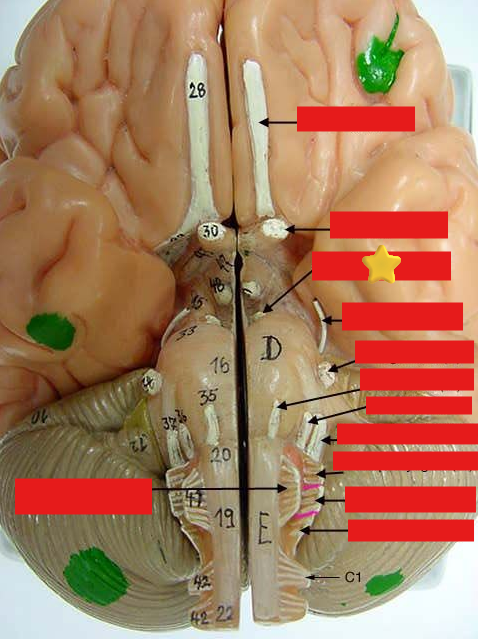

cranial nerves

12 Terms

1

olfactory

2

optic

3

oculomotor

4

trochlear

5

trigeminal

6

abucens

7

facial

8

vestibulocochlear

9

glossopharyngeal

10

vagus

11

accessory

12

hypoglossal